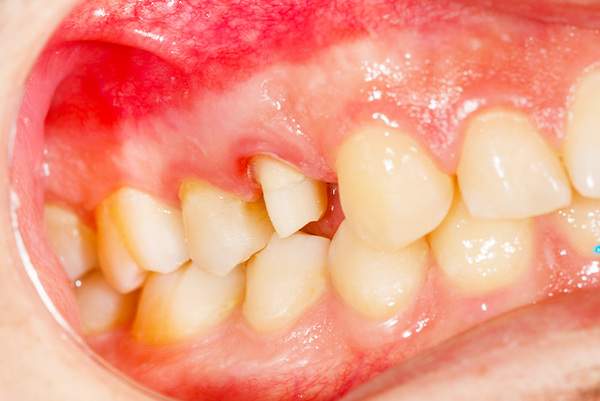

妊娠性歯肉炎

妊婦さんになると小さな命を守るために身体に様々な変化が起こります。それはお身体だけでなくお口の中にも影響を与えます。

妊娠してから歯ブラシの時に歯茎から出血するようになった、歯茎が腫れぼったいと感じている方は妊娠性歯肉炎かもしれません。

原因

妊娠すると歯肉炎にかかりやすくなってしまうのは女性ホルモン(エストロゲン)が体内で増え、それを好むある種の歯周病菌が増殖していくためです。

また、妊娠中はつわりなどでしっかり歯ブラシが行えないうえ、唾液が酸性化し口が乾燥しやすくなります。また、唾液の粘性が増すためお口の中の汚れが溜まりやすくなります。

歯周病が悪化する一因となるエストロゲンは妊娠中期〜後期にかけて増えるためこの時期に妊娠性歯肉炎を発症する方が多いです。

治療

歯肉炎の基本治療は、ブラッシング指導・歯石除去・お口の中の修復物のチェック・かみ合わせのチェック

です。

安定期にはいってからの本格的な治療をおすすめしているので、妊娠初期に出血や歯茎の腫れ・お痛みなど気になることがある場合は応急処置を行っていき、安定期にはいってから本格的な治療を行っていきます。